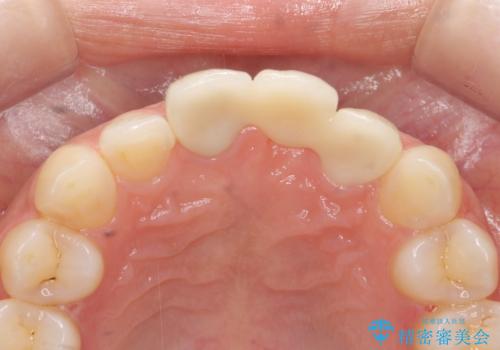

長期的な予後を見通すことが難しかったので、亀裂のある前歯の抜去を行いブリッジで審美性・機能性の回復を行いました。

- 36.3万円(仮歯・ジルコニアクラウン×3)費用は治療当時の料金となります

歯ぐきの腫れや排膿を繰り返す場合、亀裂や破折、根管の感染、歯周病等の考えうる原因を見極め、適切な処置を行うことが大切です。